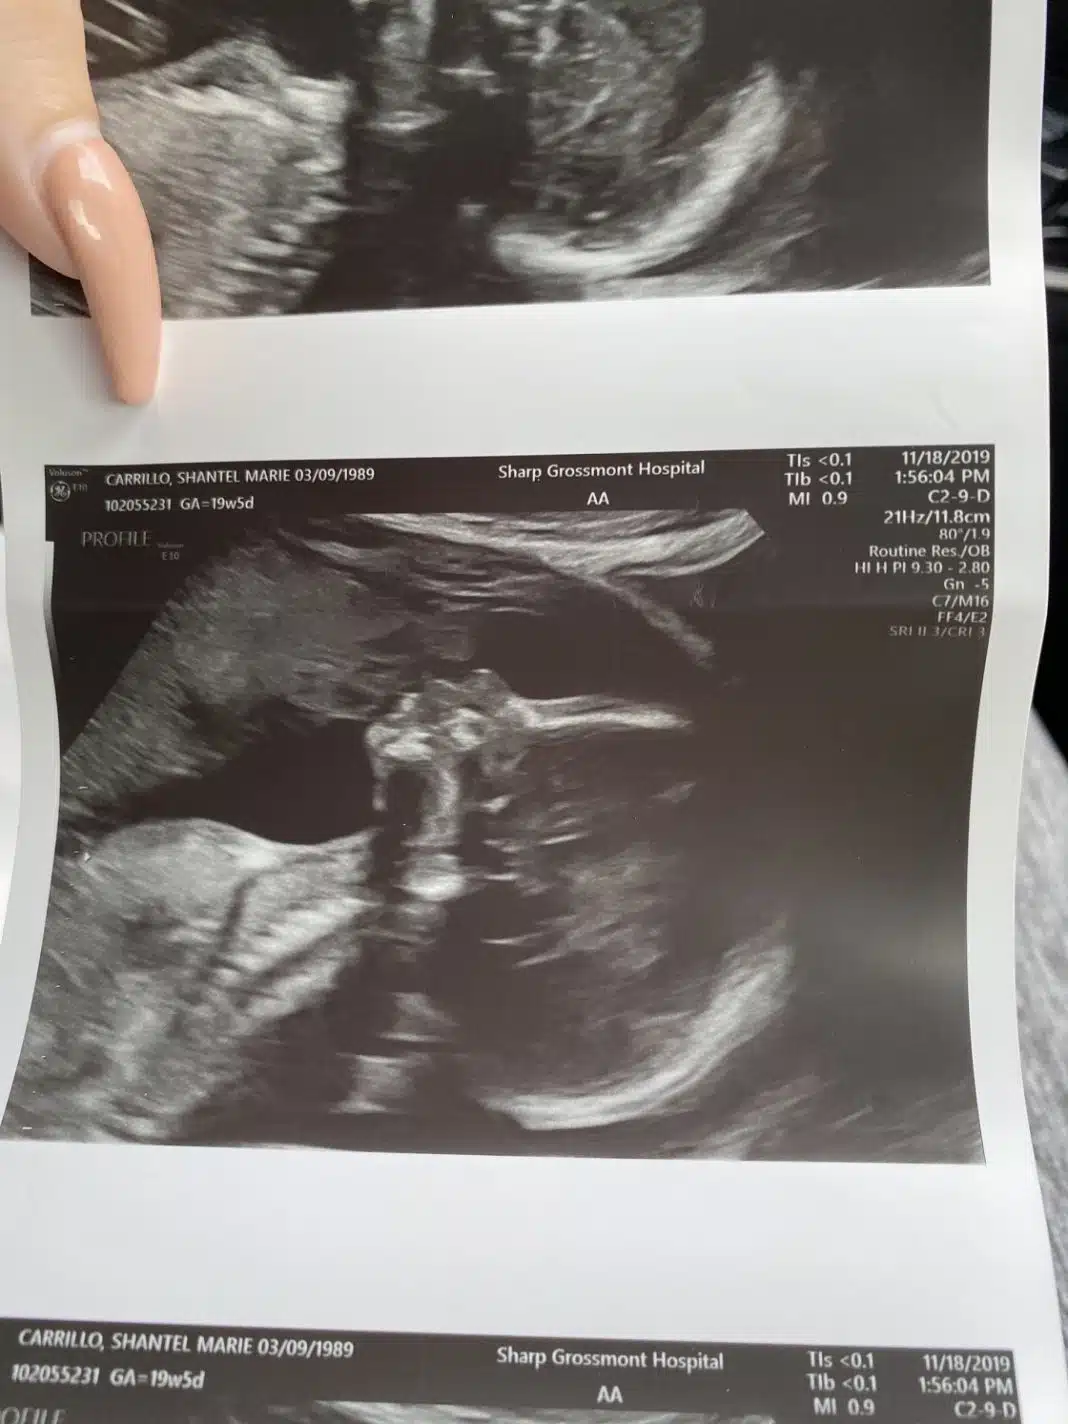

A jovel Shantel Carrillo compartilhou uma imagem de sua ultrassonografia na qual a sua bebê está com 20 semanas. De pronto, vê-se o perfil do bebê, mas, observando detalhadamente, ela, amigos e familiares entenderam que havia muito mais naquela imagem

Ao ler o comentário, a americana decidiu olhar a imagem com mais atenção. Ela realmente notou que logo acima de sua filha parecia ter o perfil de outra pessoa. Dá a impressão de que essa pessoa está beijando a bebê.

Para a mãe, contudo, não se trata do rosto de alguém desconhecido: trata-se da imagem do próprio pai, falecido em 2006. Para a jovem, o pai estava tentando se comunicar com ela e o bebê por meio da imagem.

A imagem viralizou após a gestante encontrar uma fotografia do pai segurando a neta mais velha nos braços quando nasceu, Ela disse que a foto do ultrassom também parece seu pai usando um chapéu, tornando a semelhança ainda mais especial.